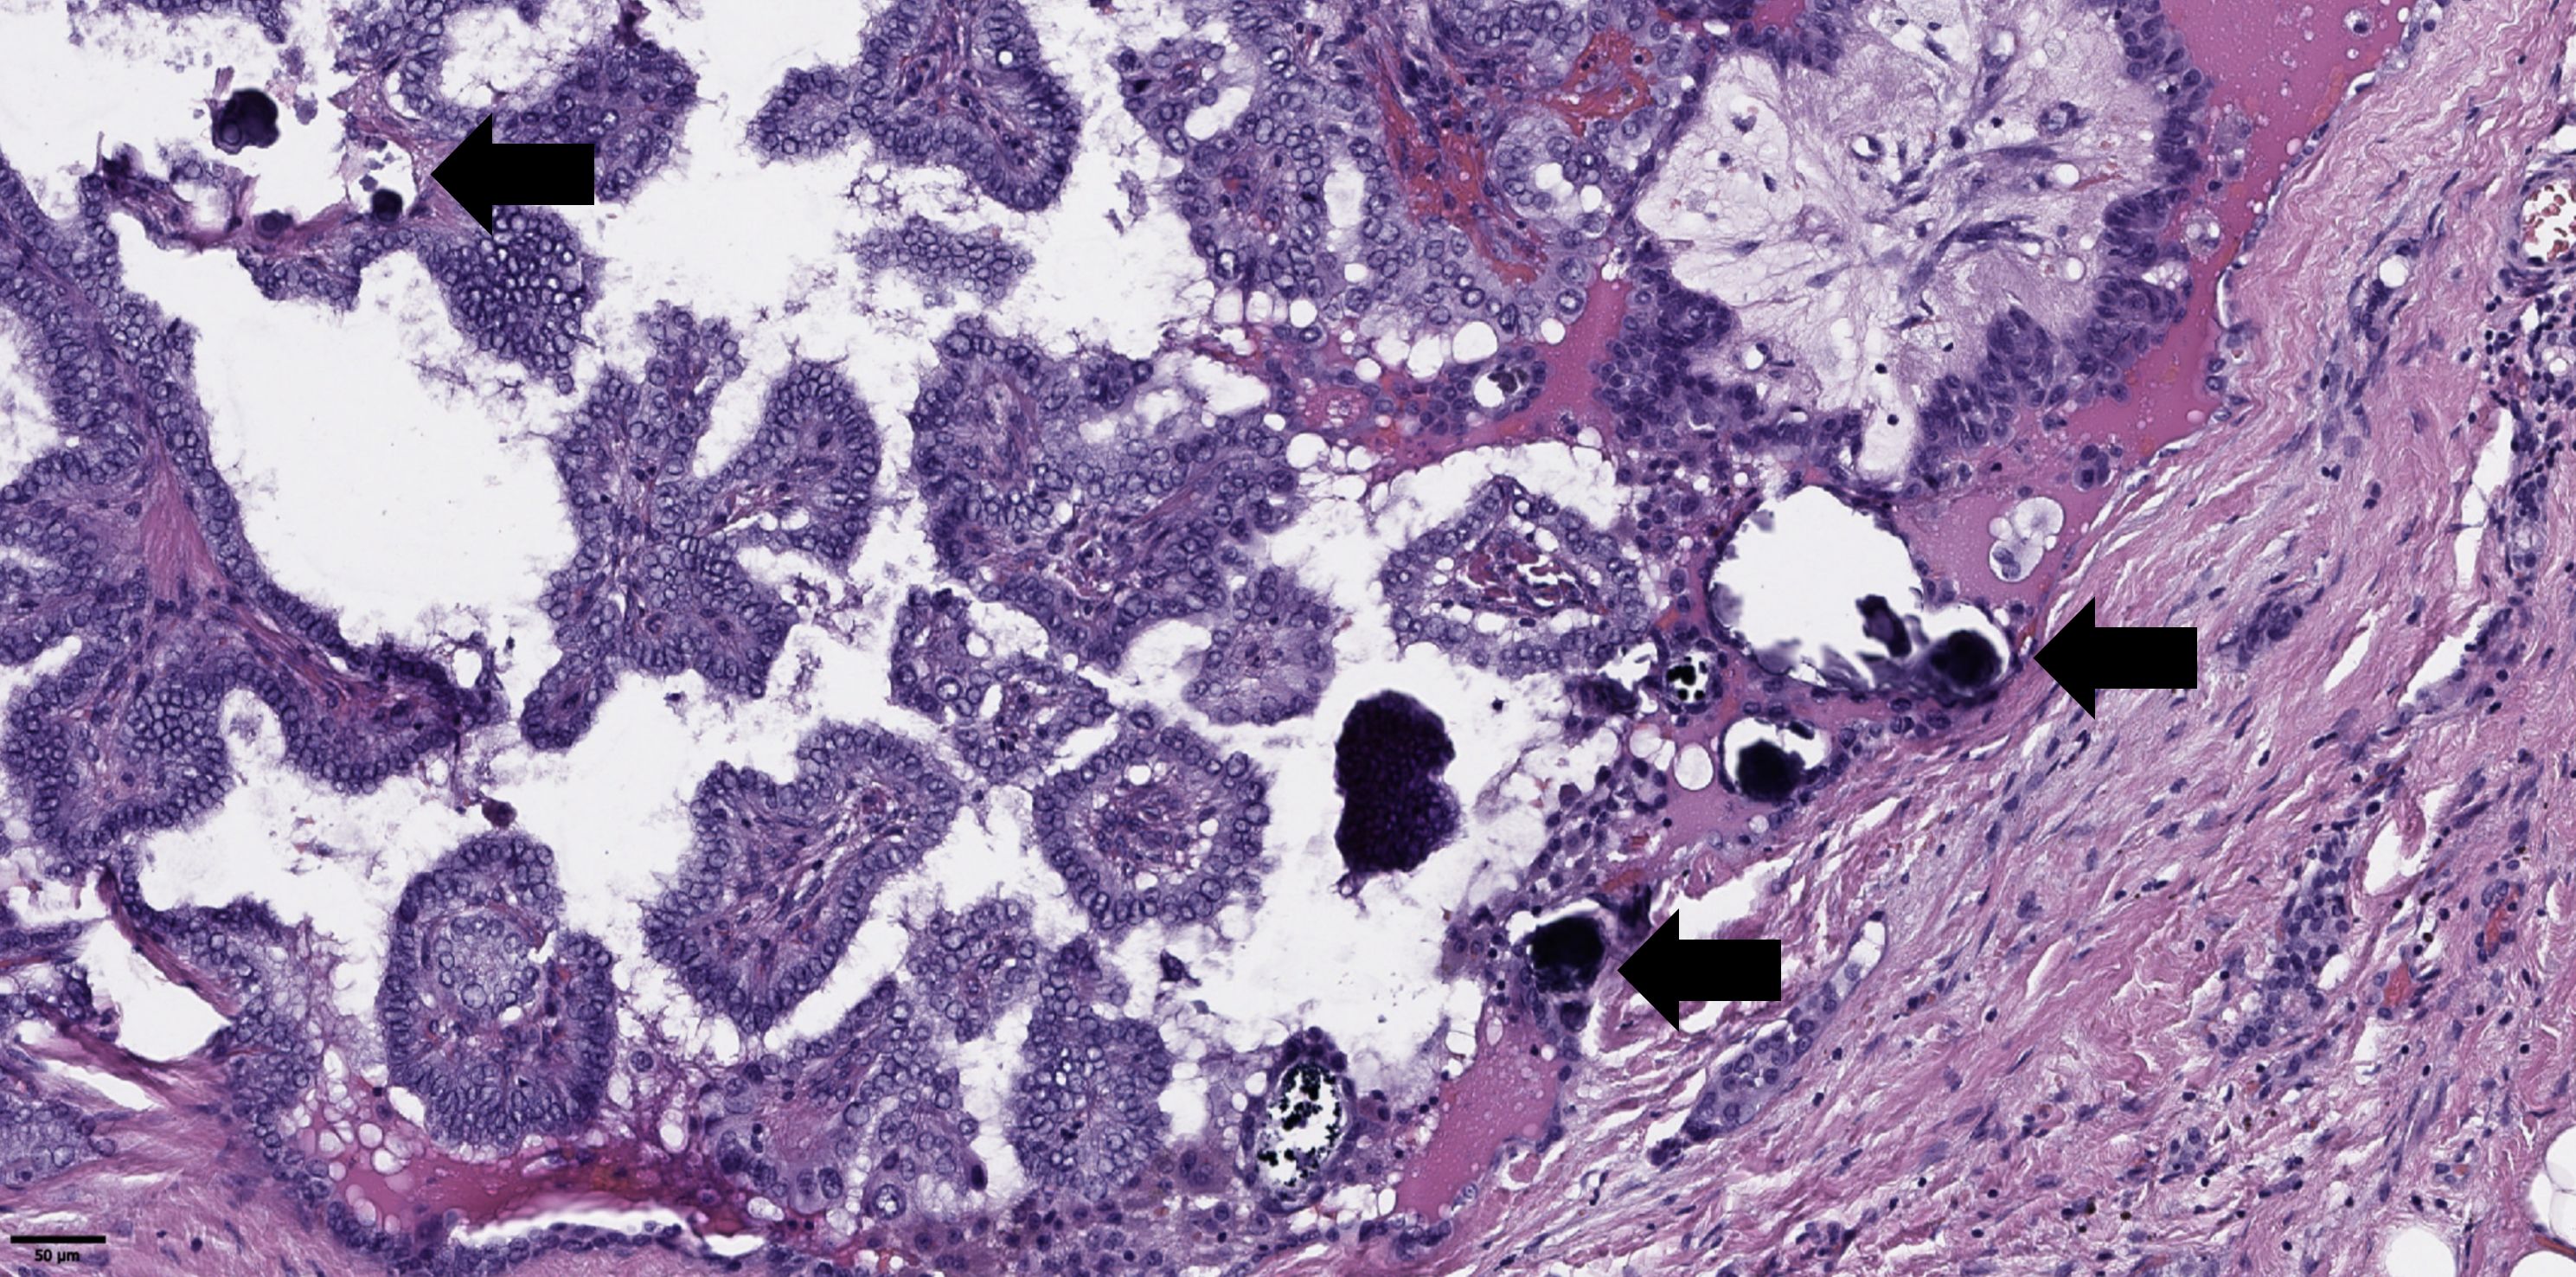

The groups were compared based on a number of tumor morphological features. The following were evaluated: the largest tumor node (Figure 1) and metastatic focus size (Figure 2), the histological subtype of papillary carcinoma according to the WHO classification (26), the presence of tall cell (Figure 3), Warthin-like, and squamous cell components in the tumor, foci of calcification and ossification in the tumor, a lymphocytic rim around the tumor node in the thyroid lobe tissue, apical vacuoles in tumor complexes, psammoma bodies in the tumor tissue (Figure 4) and in the thyroid tissue outside the tumor, the presence of a tumor capsule or its fragments, tumor “buds” (Figure 5), invasion of adipose tissue, perineural invasion, concomitant nodular thyroid diseases (tumor and non-tumor), and thyroiditis. Additionally, the following nuclear features of tumor cells were noted: angular contours, nuclear grooves, and intranuclear pseudoinclusions (Figure 6). Nucleoli in tumor cell nuclei were assessed using criteria partly adopted from the modified WHO/ISUP classification by S.A. Fuhrman for grading renal cell carcinomas (27), namely: the presence of nucleoli basophilic, visible but not prominent at ×100, or nucleoli conspicuous at ×100, basophilic, or nucleoli conspicuous at ×100, eosinophilic at ×400. Furthermore, the number of mitotic figures per 2 mm² of tumor tissue in “hot spots” and the presence of atypical mitotic figures were assessed. The degree of tumor fibrosis was visually graded as 0 (no fibrosis), 1 (fibrosis in less than 50% of the tumor node), or 2 (fibrosis in 50% or more of the tumor node) (Figure 7). A tumor “bud” was defined as a tumor complex no larger than 0.1 cm in diameter, located no more than 0.1 cm far from the tumor node, with one or more non-neoplastic thyroid follicles between them, which could not be reliably differentiated during routine histological examination between a tumor embolus in a vessel lumen (blood or lymphatic), an additional independent microfocus of tumor growth, or a tangential section of a tumor invasion area into adjacent thyroid tissue.

Figure 4. Histological images of psammoma bodies in tumor of papillary thyroid microcarcinoma (black arrows). Hematoxylin–eosin, х100.

Regarding the higher frequency of psammoma bodies in tumor tissue and the statistical trend toward more frequent detection of psammoma bodies outside the tumor in patients with metastases, similar findings have been reported in large studies by Bai et al. and Pyo et al. (31, 32). Unfortunately, Bai et al. did not specify whether psammoma bodies were detected in tumor tissue or in thyroid tissue outside the tumor. Additionally, the study group in that work consisted of patients with tumor nodes ≥1 cm (mostly ≥2 cm). Pyo et al. included patients with papillary microcarcinomas as well as larger tumors, and approximately 30% of the overall group had multifocal tumor growth. In that study, the presence of psammoma bodies in both tumor tissue and thyroid tissue outside the tumor showed statistical significance for regional metastasis detection. Unfortunately, in our study, the detection of psammoma bodies outside the tumor showed only a statistical trend toward more frequent synchronous metastasis detection. Moreover, there are differences in statistical methods. However, the association between psammoma bodies in tumor tissue and regional lymph node metastases was confirmed in both univariate and multivariate analyses. Furthermore, our findings align well with the results of J.V. Johannessen and M. Sobrinho-Simões, who suggested that psammoma bodies may represent calcified papillary tumor structures or tumor emboli in lymphatic vessels (33). Additionally, Liu et al. (34) noted that intra- and extratumoral microcalcifications detected during ultrasound examinations of patients with papillary thyroid cancer are risk factors for cervical lymph node metastases. The association between patient age and the risk of synchronous regional lymph node metastases identified in our study also correlates well with the results of Liu et al.: we found an increased risk of metastases in patients younger than 52 years, while Liu et al. reported an increased risk in patients younger than 55 years.